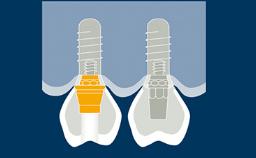

Ao fornecer a um paciente uma reabilitação sobre implante, os clínicos devem decidir se fabricam uma prótese provisória ou se vão diretamente para a prótese definitiva. Vários fatores desempenham um papel na tomada da decisão correta. Estes envolvem a localização do implante em região anterior ou posterior, o número de implantes, a necessidade de moldar o tecido, como é frequentemente visto com implantes adjacentes à região anterior, e a necessidade de suporte oclusal. Os desejos do paciente também podem desempenhar um papel nesta decisão. Este módulo irá destacar as indicações, materiais e técnicas para a fabricação e utilização de uma prótese provisória implantossuportada.